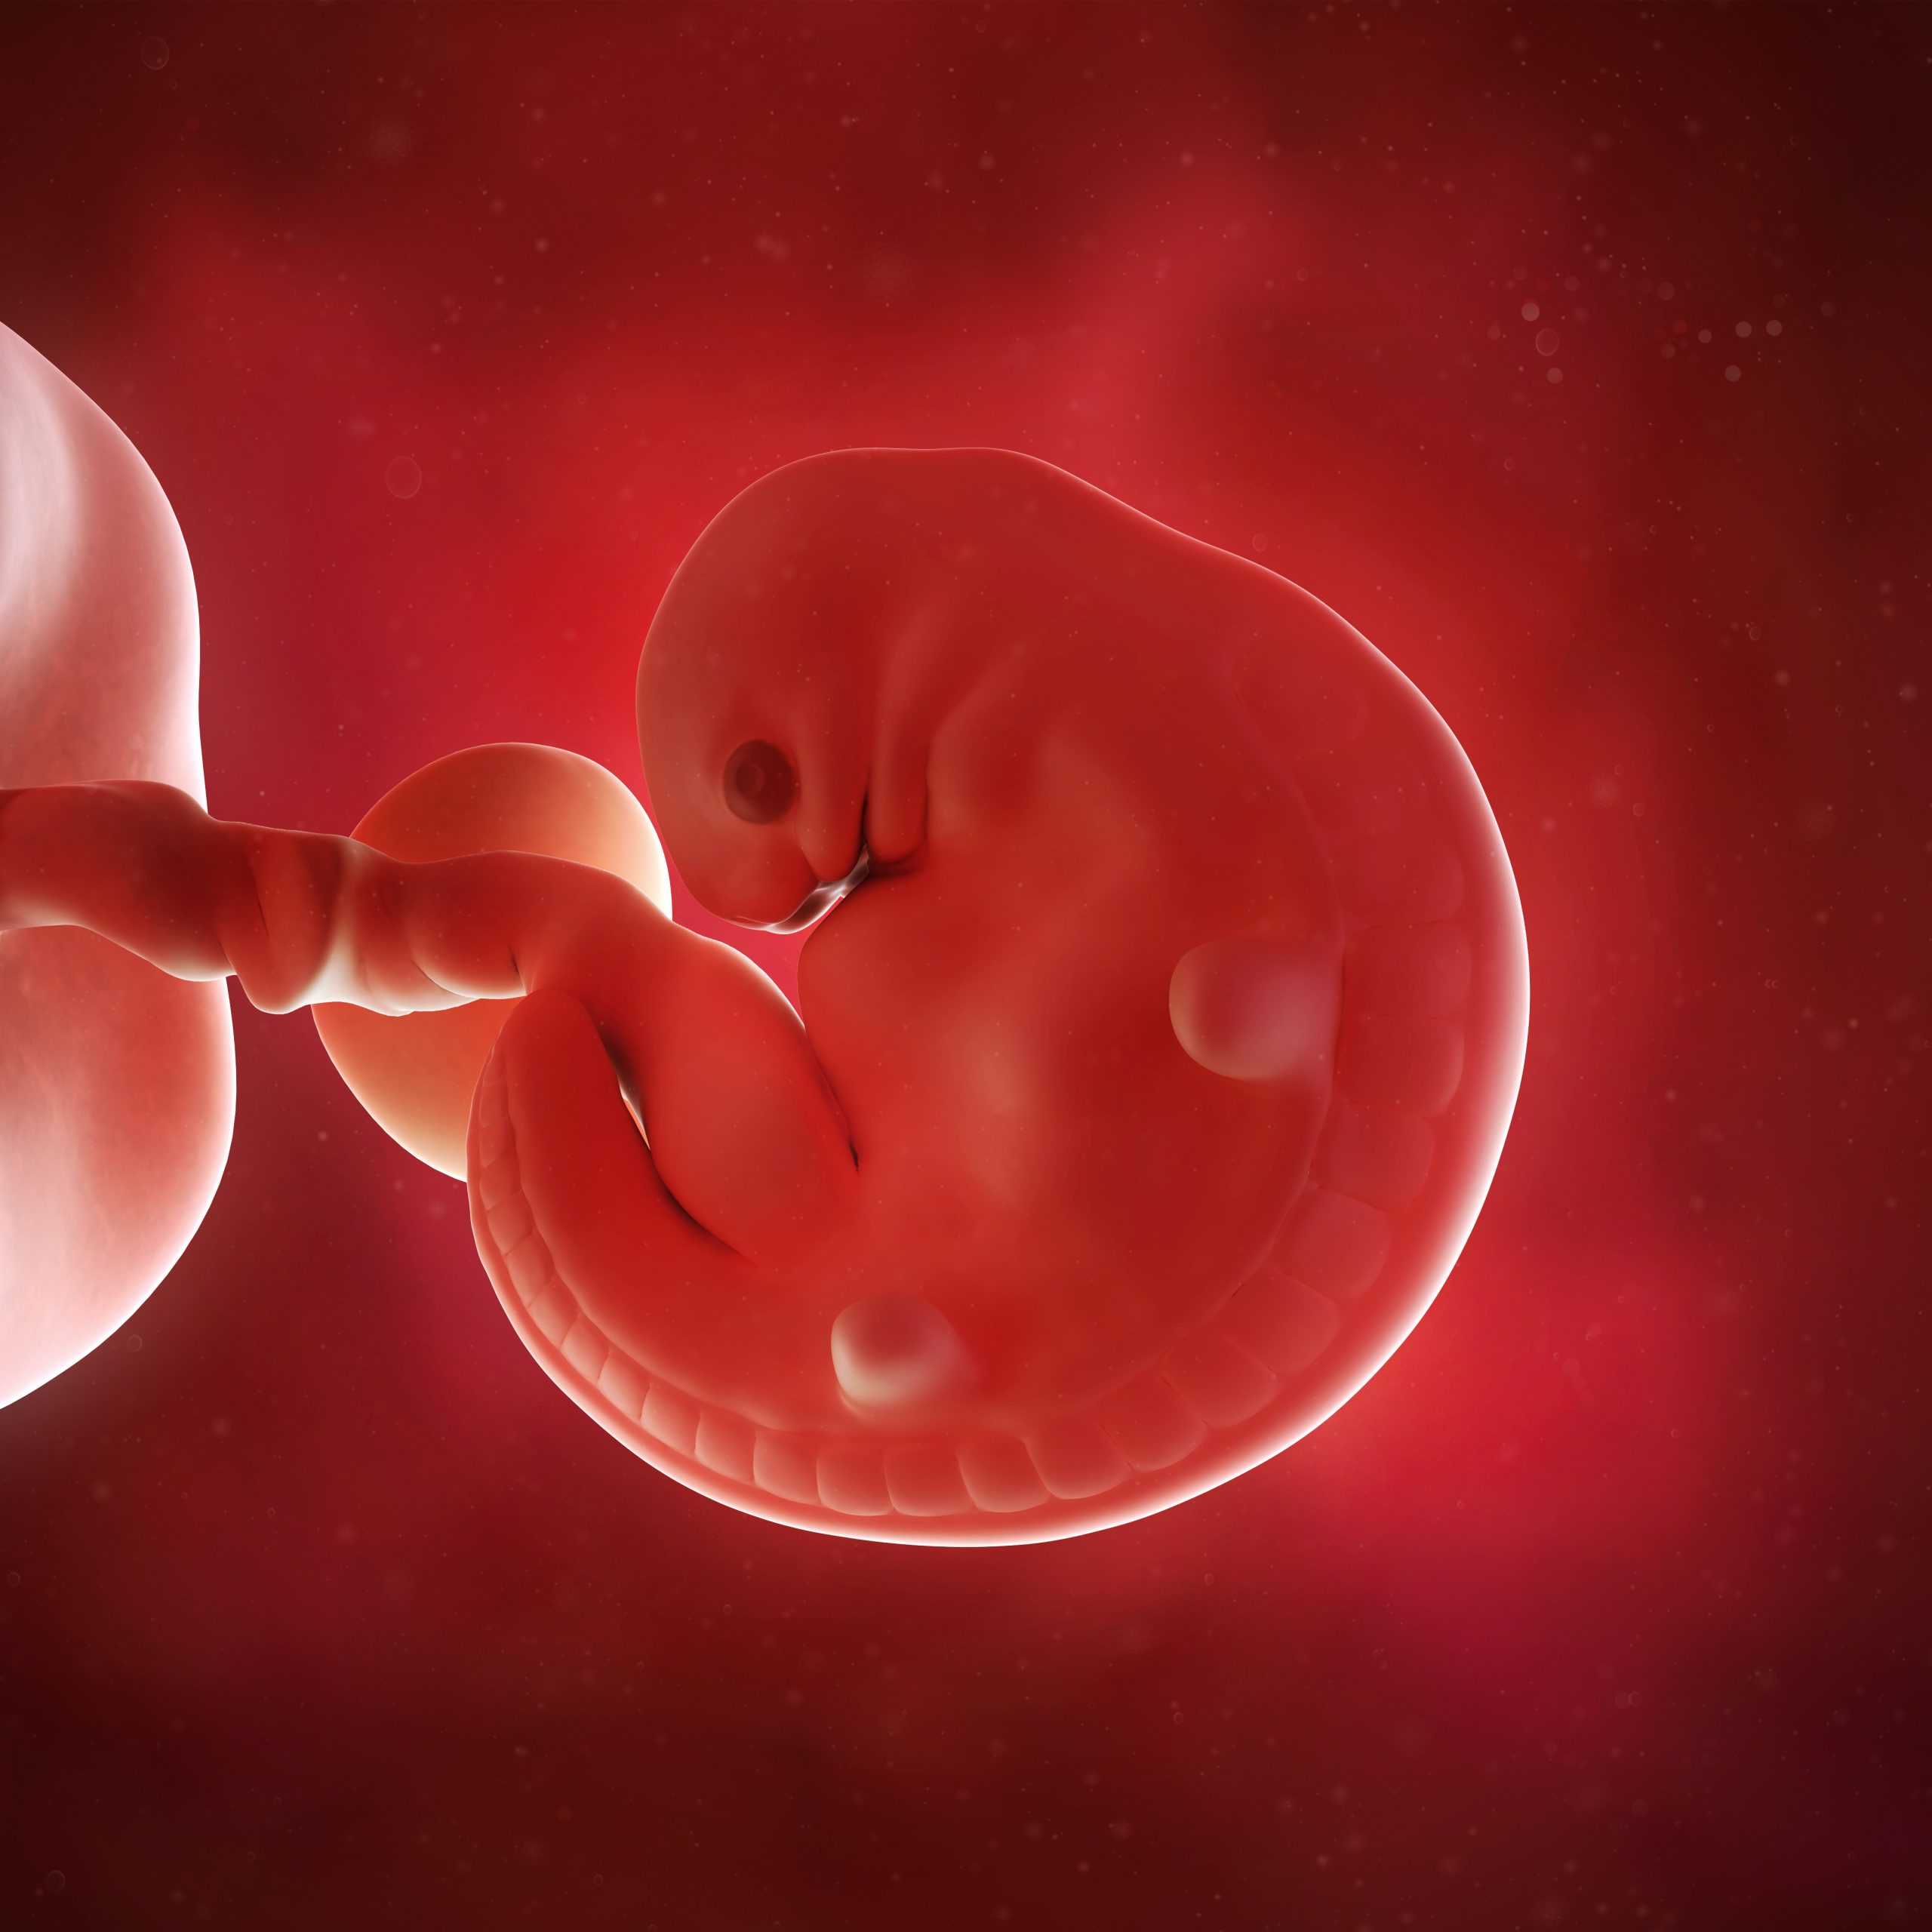

Этот период характеризуется формированием у эмбриона черт лица, а также развитием нижних и верхних конечностей. В глазах образуется сетчатка, верхние конечности способны сгибаться в локтях, и нижние — в коленях.

Ваш ребенок размером с фасоль.Вы еще этого не почувствуете, но ее тело тоже похоже на крошечную прыгающую бобу, двигающуюся урывками (Мур и др., 2019a).Голова вашего ребенка больше туловища и наклонена к груди (Мур и др., 2019a). Ее черты лица постепенно становятся более четкими по мере обретения формы верхней челюсти и носа (Hill 2019a, Moore et al 2019b, Visembryo nda, b). У нее есть небольшие холмики, где будет расти оболочка ее ушей (Hill 2019b, Moore et al 2019a, Visembryo ndb), и ее глаза теперь более очевидны (Hill 2019b, Moore et al 2019a, Visembryo nd a), а складки век частично закрывают их (Hill 2019c, Moore et al 2019c, Tawfik et al 2016).

Нервные клетки в мозгу вашего ребенка разветвляются, чтобы сформировать ранние нейронные пути (Hill 2019d, Moore et al 2019d). Часть мозга, отвечающая за ее обоняние, также принимает форму (Hill 2019d, Moore et al 2019d). На руках вашего ребенка появляются выступы там, где будут его пальцы (Mooney 2016a, Moore et al 2019). Ее ноги формируются, и форма ступней начинает проявляться. У нее еще не будет кончиков пальцев на ногах. Ее ноги и ступни развиваются примерно на пять дней позже, чем руки и кисти (Муни и др., 2016b, Мур и др., 2019).Ее эмбриональный хвост почти исчез, он снова сокращается, образуя копчик (копчик) (Mukhopadhyay et al 2012).Узнайте, как беременность может повлиять на ваше тело и вашу жизнь на восьмой неделе беременности.